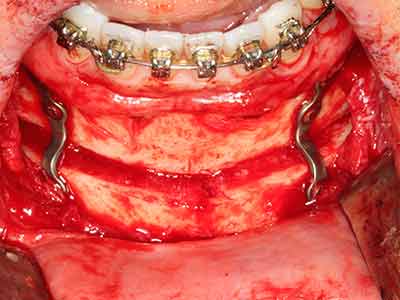

Пиезохирургията има допълнителни предимства при събиране на костни блокове. В допълнение към високата прецизност при остеотомията, описана по-горе, употребата на фините режещи накрайници значително намаляват загубата на материал. Голяма загуба на материал по време на събиране може да се очаква с дебелите накрайници, особено при употреба на борери Линдеман (Lakshmiganthan, Gokulanathan et al. 2012). Базалното разделяне, което е необходимо, особено за присадка на блок при ретромолар, е улеснено от специално създадени правоъгълни триони. В резултат на това, пиезохирургията е разглеждана като прецизна, улеснена и безопасна процедура за събиране на костни блокове в ретромоларното пространство (Happe 2007) (Фиг. 1-12).

Костната тъкан е не само минерализирана структура, тя съдържа и съществено количество колагенови влакна. Това означава, че тя има не само добра компресивна сила, но и известна степен на гъвкавост, която може да се възприеме като предимство при извършване на костна аугментация. В класическата процедура по разширяване чрез костно разделяне, атрофиралият алвеоларен гребен е разделен надлъжно и внимателно разширен след достигане на подходящата остеотомна дълбочина (Фиг. 13-16), в идеалния случай без допълнително отстраняване на периостеума (Brugnami, Caiazzo et al. 2014, Stricker, Fleiner et al. 2014). Системите с винт и пластини с увеличаване на разстоянието при разширяване са доказали ефективността си при разделяне на двете костни ламели, оставайки под прага на фрактурите. В общи линии, оставащата ширина на костта от поне 3–4 mm е задължителна (Chiapasco, Zaniboni et al. 2006), за да се гарантира добра гъвкавост и достатъчно костно покритие за бъдещото поставяне на импланти. Ако е необходимо, вертикалната остеотомия на едната или двете страни може да подобри гъвкавостта. Комбинацията с допълнителни техники за аугментация, особено в букалната страна, е описана като алтернатива на класическата техника.